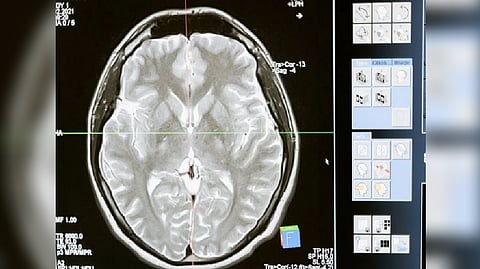

OL cells generate the insulating coating around neurons, called myelin. The study, published online in the journal Nature Communications, provides detailed insight into the entire process of how these changes in the genes that regulate cell metabolism impair the development of OLs, as well as the therapeutic value of treating HD with high doses of thiamine and biotin. Thiamine and biotin are both B vitamins and are involved in a wide range of metabolic processes that help keep the nervous system healthy.

Using advanced modeling methods, researchers confirmed that in mouse and human HD brain tissue, the maturation state of OL cells and their precursors are arrested in intermediate development, impairing production of the myelin that is critical for neuronal health and function. They found that high doses of thiamine and biotin were connected to significant rescue of gene expression changes in OL cells.